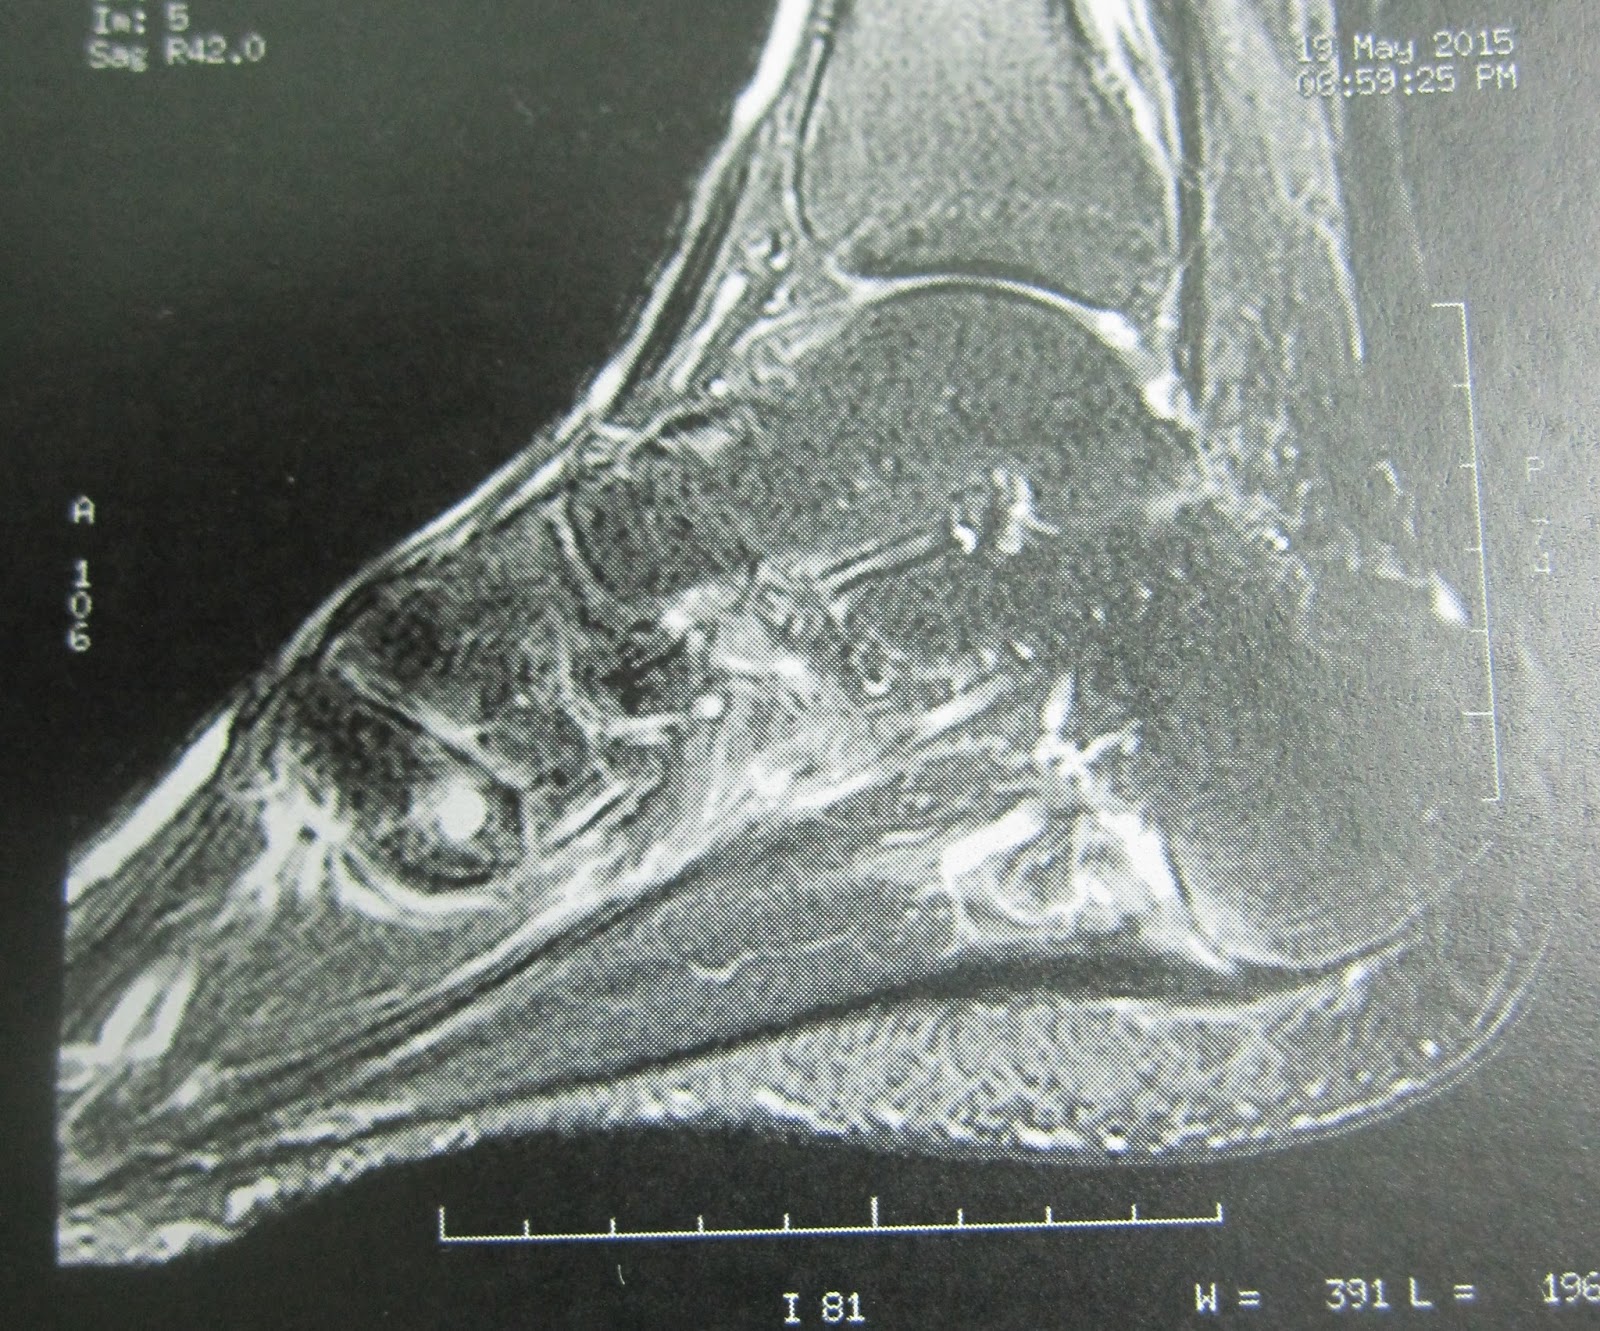

Antes de operar con el TOPAZ, confirmo y me aseguro en todo lo posible del diagnóstico. Se realiza una Resonancia Magnética y el informe dice lo siguiente: engrosamiento de la fascia a nivel de su inserción y el el primer tercio distal con rotura parcial de la misma y signos inflamatorios, signos compatibles con fascitis plantar. Este es el informe del radiólogo.

Yo llego a la conclusión que el paciente tiene fascitis por la inflamación, fasciosis por la degeneración y engrosamiento de la fascia y rotura parcial de la misma.